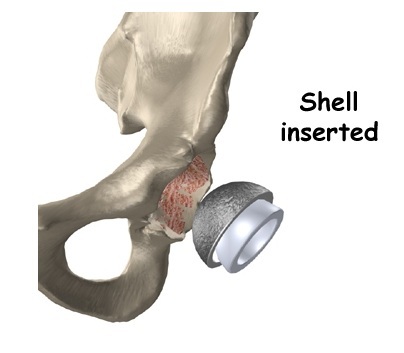

Bước 2: Phần sụn khớp bị tổn thương của hõm khớp sẽ được làm sạch. Hõm khớp sẽ được chuẩn bị để phù hợp với kích thước của hõm khớp nhân tạo được lựa chọn.

Bước 3: Đặt hõm khớp nhân tạo. Hõm khớp nhân tạo sẽ được đặt vào ổ khớp đã được chuẩn bị và cố định. Hõm khớp nhân tạo sẽ được cố định bằng xi măng sinh học (nếu khớp nhân tạo có xi măng) hoặc bằng các vít cố định( nếu bộ khớp nhân tạo không xi măng).